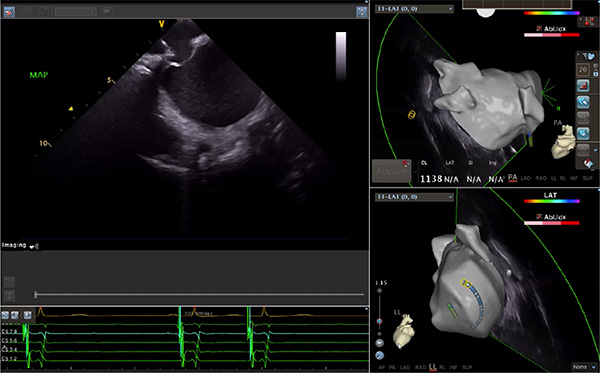

超聲心動圖技術包括常規(guī)經胸超聲(TTE)、經食管超聲(TEE)、心腔內超聲(ICE)、超聲聲學造影(MCE)、三維超聲心動圖等,ICE是一種新興技術——將微型的換能器安裝在心導管的尖端,經由外周血管輸送至心腔內部,換能器發(fā)射聲波,對心臟及其鄰近組織進行實時高質量成像和(或)血流動力學測定的超聲成像技術。基于不同的技術原理,心腔內超聲導管被分為兩類:機械旋轉式超聲導管和相控陣超聲導管。目前,臨床上主要應用的是相控陣超聲導管,ICE成像通過術者旋轉導管及操縱導管手柄上的兩個旋鈕來完成。

ICE門檻高、集成了超聲和圖像處理最前端的技術,是當前內窺超聲方向最挑戰(zhàn)的領域。不同于傳統(tǒng)接觸式三維重建方法會產生假腔,影響術者對靶點或結構的判斷,心腔內超聲(ICE)可直接顯示心臟結構,有助于理解心臟內各部位之間的解剖關系,不僅具有實時成像、并發(fā)癥監(jiān)測以及良好的耐受性,同時以股靜脈入路,無需全麻或深度鎮(zhèn)靜,日益成為心臟介入手術中重要輔助工具,被譽為心臟介入醫(yī)生的“黃金眼”。心腔內超聲可用于多種心臟介入手術,潛在患者群體龐大,動脈網測算我國心腔內超聲導管市場空間或將超100億元,具有廣闊前景。

隨著心腔內超聲的應用更廣,性能也在逐漸優(yōu)化,已從二維成像轉變?yōu)?strong>三維成像,極大增強了引導及可視化能力。二維心腔內超聲支持雙平面或三平面成像,可顯示兩個或三個不同的平面視圖,但醫(yī)生需將這些圖像在腦海中重新構建為三維解剖結構。三維心腔內超聲則可直接呈現(xiàn)三維解剖結構圖,便于醫(yī)生更輕松地開展手術。按照產品發(fā)展方向,預計心腔內超聲還將向更清晰、精準、多功能等方向發(fā)展。